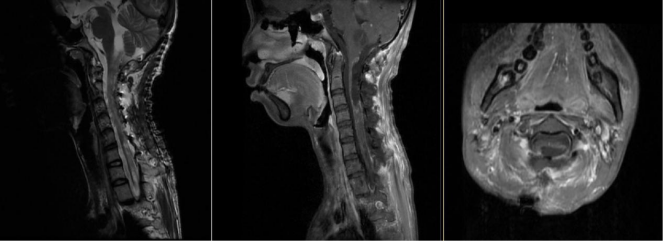

图2 术前造影显示肿瘤血供丰富,左、右椎动脉均有供血

其实雯雯罹患的是一种常染色体显性遗传病——Von Hippel-Lindau综合征,这种病会造成中枢神经系统的多发血管母细胞瘤,同时还常合并肾脏或胰腺囊肿、嗜铬细胞瘤、肾癌以及外皮囊腺瘤等疾病,目前主要以手术治疗为主。对于有家族遗传史的病人,妊娠期需要做基因筛查,优生优育。考虑到雯雯目前病情紧急,已经出现四肢瘫痪和呼吸困难,住院后王贵怀教授团队紧急讨论制定了手术方案,先期处理延颈髓巨大血管母细胞瘤,术前行全脑和脊髓血管造影,明确肿瘤血供,彻底切除病灶。